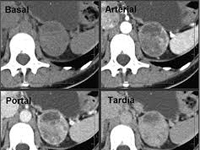

Urología![]() |